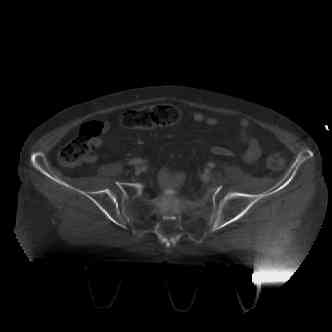

attached are several CT cuts. please let me know if you need more. the CT is pre-pelvic ex-fix placement.

Имя     : image005.jpg